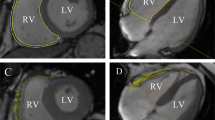

A set of short-axis and long-axis two-chamber and four-chamber slices were uploaded into the tissue-tracking module. Only short-axis slices were used to analyze cardiac function while both short- and long-axis slices were used to analyze strain parameters. An experienced radiologist manually delineated the endocardial and epicardial borders in the LV end-diastolic and end-systolic phases for each series involving short-axis two-chamber and four-chamber cine images; the moderator bands and papillary muscles were carefully excluded. Finally, reference lines were marked in the LV long-axis two-chamber and four-chamber cine images, and the short-axis reference points were defined as shown in Fig. 1.

Global strain parameters of subgroups are shown in Table 2. The LV global radial, circumferential, and longitudinal PS were lower in the reduced-LVEF group as compared to the control group (all P < 0.001). Although there were no significant differences between the preserved-LVEF group and the control group in the LV global radial and circumferential PS (P > 0.05), global longitudinal PS was lower in the preserved-LVEF group as compared to the control group (− 15.93 ± 3.12% vs. − 17.79 ± 2.02%, P = 0.005) (Fig. 2).

Regional LV strain parameters (including those of the basal, mid, and apical segments) of the three groups were compared (Supplementary table). Most regional radial, circumferential, and longitudinal LV strain parameters were significantly different between the reduced-LVEF group and control group (all P < 0.05). Longitudinal and circumferential PDSR of the basal segment and longitudinal PDSR of the mid segment were lower in the preserved-LVEF group as compared to the control group (all P < 0.05). In addition, the radial PS of the apical segment was higher in the preserved-LVEF group as compared to the control group (58.97 ± 13.61% vs. 51.35 ± 18.04%, P = 0.037) (Fig. 3).